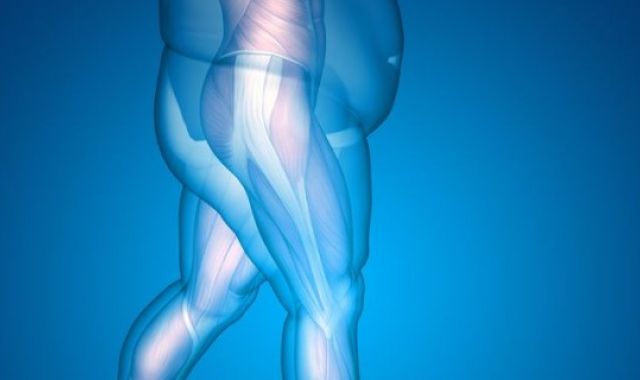

Obesity and Joint Replacement Surgery

Obesity is major problem facing our affluent society. In 2014-2015, a staggering 63.4...